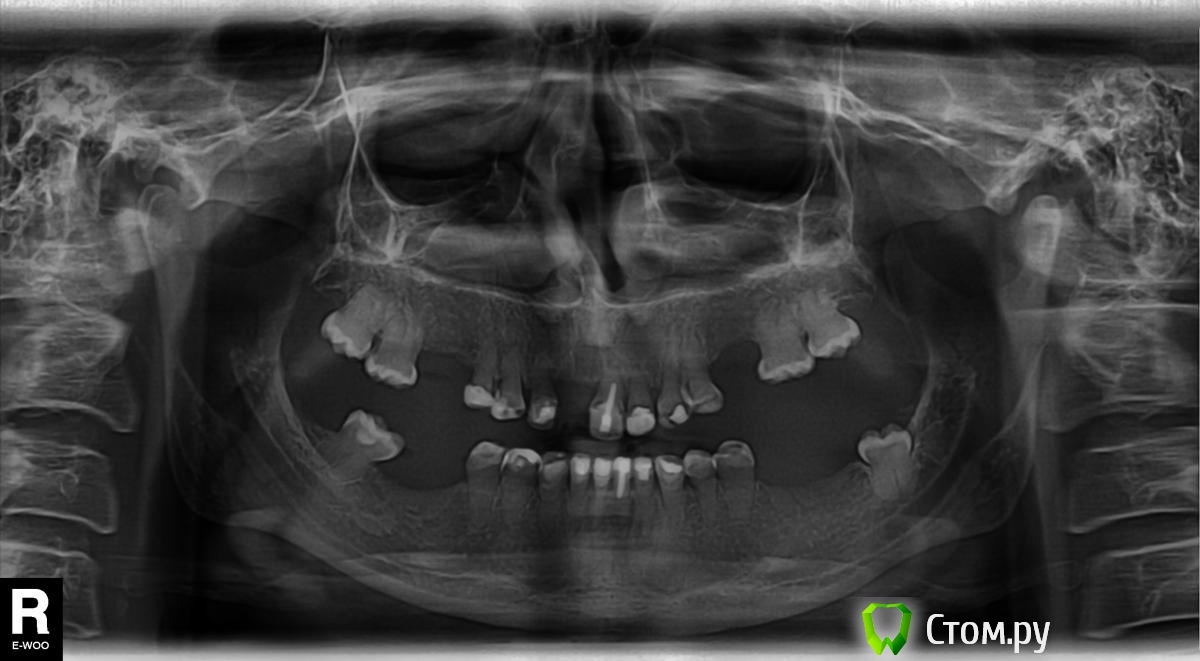

Евгения Gor Опубликовано 24 ноября, 2014 Автор Поделиться Опубликовано 24 ноября, 2014 Здравствуйте!У меня наследственное заболевание Синдром Стептона-Капдепона.С 16 лет оставшиеся зубы были нарощены композитом,сейчас мне 30.Нет нижних 6-ок и 7-ок, сейчас на их месте сделана костная пластика под импланты.Вверху нет 6-ок и правого переднего, что скрывалось съемным протезом.Высокая стираемость привела к глубокому прикусу. Сейчас врач посоветовал исправить его временными коронками,а после приживления имплантов и исправления прикуса ставить постоянные циркониевые коронки.Подскажите можно ли обойтись повторным наращиванием,боюсь что из-за глубокого прикуса зубы в коронках быстро расшатаются и выпадут,т.к. корни при таком заболевании очень короткие и шаткие. Специалистов имеющих опыт с таким заболеванием в городе нет.Есть ли другие способы? Ссылка на комментарий

Евгения Gor Опубликовано 24 ноября, 2014 Автор Поделиться Опубликовано 24 ноября, 2014 Снимок ОПТГ Ссылка на комментарий